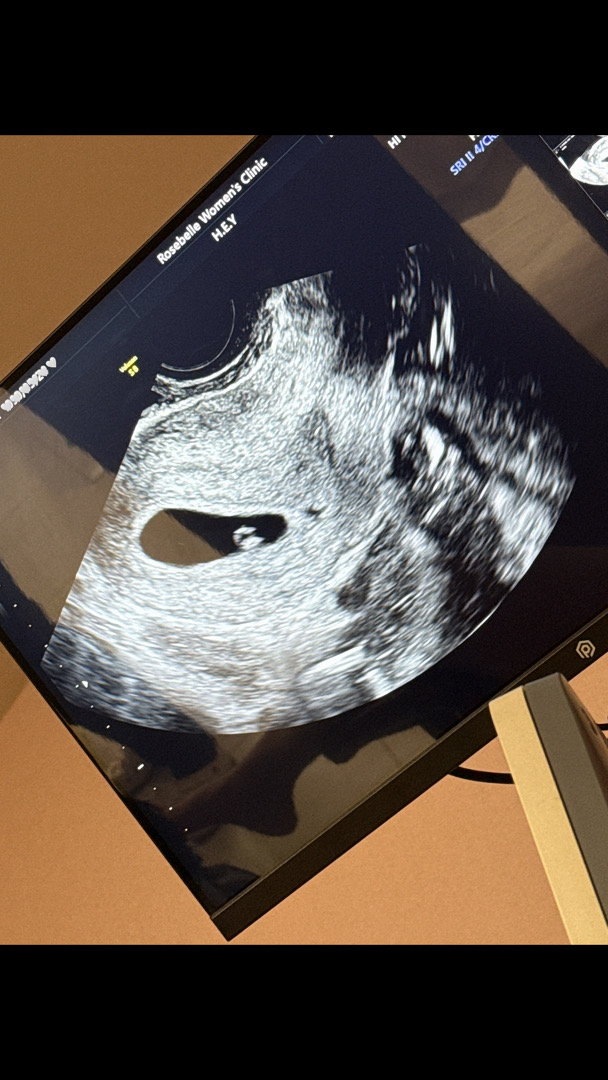

6주1일차 초음파 사진입니다 갈색혈이 나와서 병원방문했는데 심장소리도 듣고 왔어요 ! 다른분 초음파 사진 보면 난황 옆 아기모습도 보이는 것 같은데 제 초음파에선 안보이는거 같고 입덧도 없고 컨디션도 평소랑 일정해서 불안하네요 ㅠㅠㅠ 저처럼 입덧 없으신분 계신가요 🥹 혹시 다들 아가 언제 보셨나요?